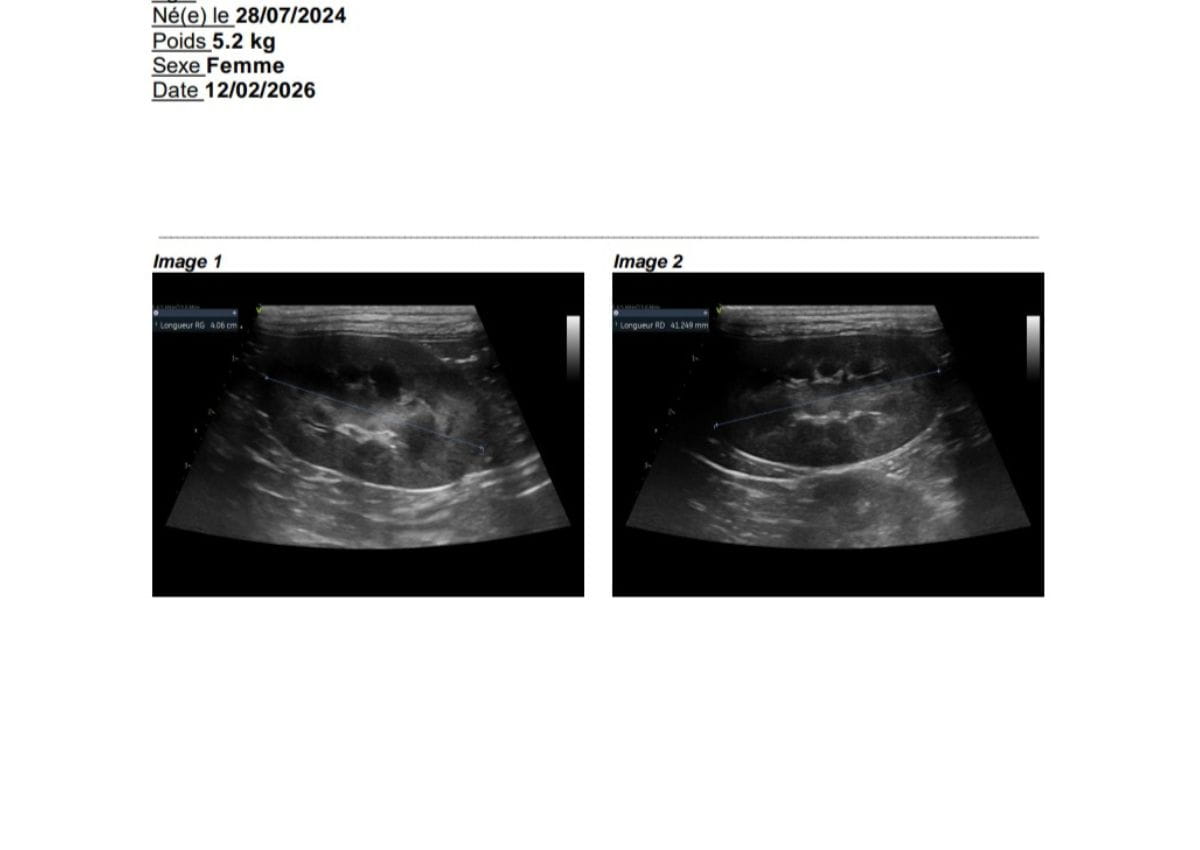

En complément, des échographies cardiaques et rénales sont souvent réalisées afin de suivre la santé des reproducteurs.